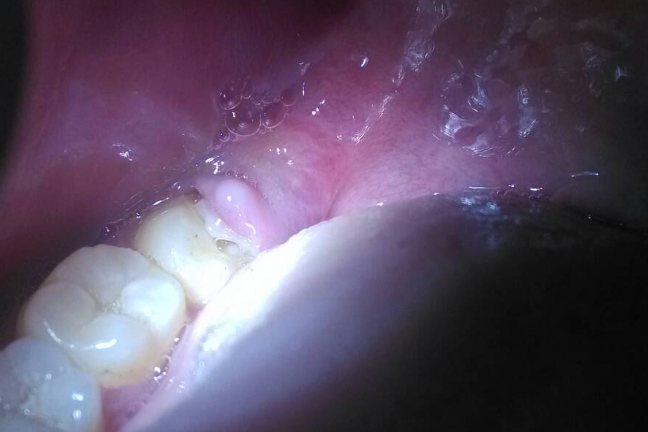

上火牙疼主要表现为牙龈红肿,牙齿和周围的牙龈软组织充血发红,肿胀隆起,淋巴肿痛,一般伴有舌苔黄厚,口苦,牙齿松动,冠周脓肿不敢咬合或者吞咽疼痛或者张口受限或者脸肿等症状。